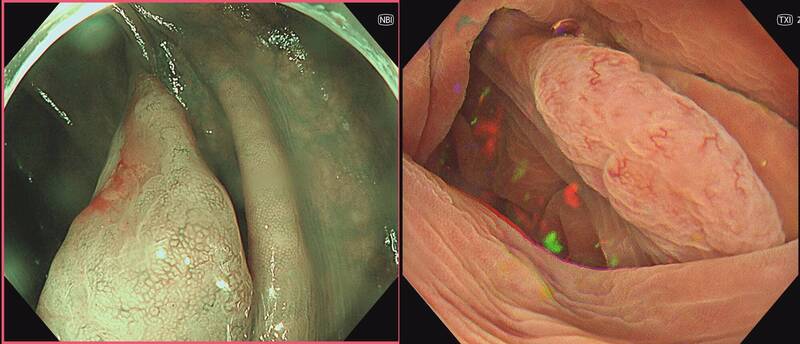

〔健康頻道/綜合報導〕若有大瘜肉,多數人會至醫院,但這類治療不能在診所嗎?禾馨民權內科診所腸胃科醫師葉秉威分享,有名40多歲女性,大腸內約有2.5至3公分的鋸齒狀瘜肉,就診時表示,希望在診所進行手術。經評估後,決定安排水下內視鏡黏膜切除術(UEMR)完整摘除瘜肉。在接受切除手術後,該名患者恢復良好,也沒併發症發生,病理也證實完整切除,免去病患的煩惱。

針對該名患者使用的水下內視鏡黏膜切除術優點,葉秉威在臉書專頁「胃腸專家 葉秉威醫師」發文說明,其不僅切除完整率、復發率較傳統內視鏡黏膜切除術高,併發症風險也與傳統方式相當。

對於大瘜肉的定義,葉秉威解釋,一般超過1公分大腸瘜肉,就叫做進階型瘜肉,也是認知中較大的瘜肉,因為這類瘜肉多帶著較高癌變風險,也較容易切不乾淨,或容易復發,因此需要醫師特別留意、小心切除。